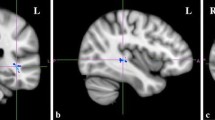

DTI

There were no relationships between AQ-28-score and FA-values in the Exploration study. Therefore we pooled the data (N = 508) and reran the analyses with threshold free cluster enhancement and corrected for multiple comparisons with family wise error correction (p < 0.05). No significant associations were found.